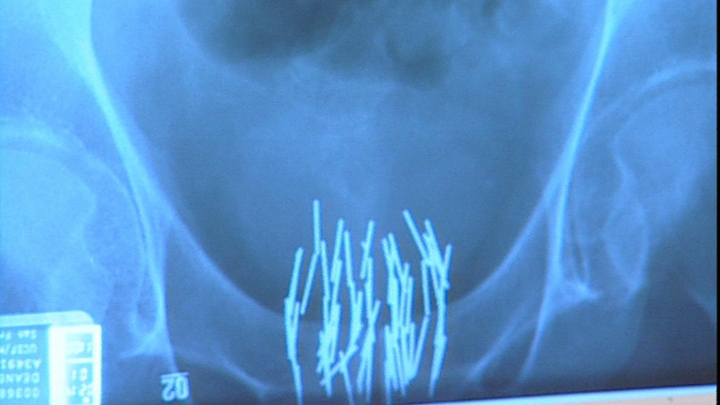

The normal treatment for prostate cancer involves surgery or radiation, but these can have serious side effects such as impotence and incontinence. A new treatment avoids the side-effects, using simple metal rods and magnets. The magnets heat the rods inserted within the prostate to just the right temperature to kill the cancer cells.